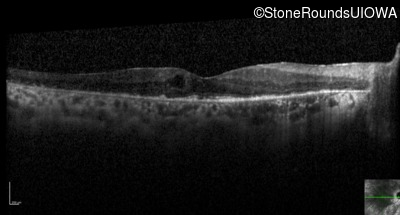

Optical Coherence Tomography - Left - 20/100

Exemplar / OCT Stack